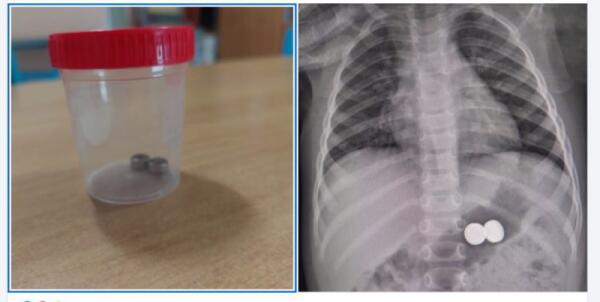

BIMBA DI UN ANNO INGERISCE BATTERIE: SALVATA DAI MEDICI DEL GARIBALDI-NESIMA